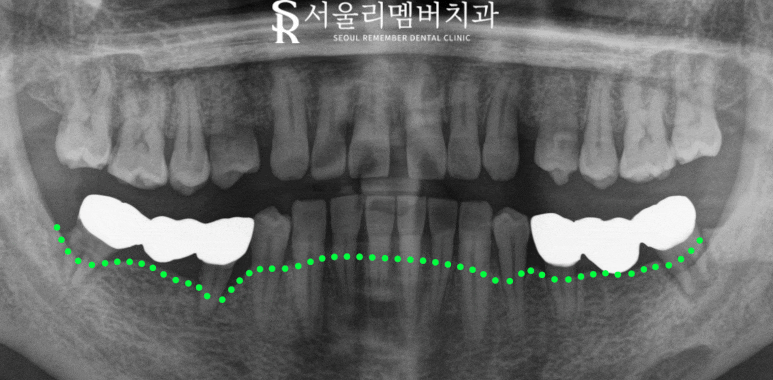

일단 정확한 진단을 위해

구강 카메라로 찍어봤습니다.

곳곳에 있는 치석과 퇴축된 잇몸을 보아

확실히 관리가 안 된 상태를 볼 수 있는데요.

이러면 염증으로 치조골까지 흡수했을 가능성이 높아

신속하게 x-ray도 촬영했습니다.

예상했던 대로 치조골이 많이 퇴축되었는데요.

크라운을 수복했던 치아들 뿌리가

힘들게 매달려 있는 걸 볼 수 있습니다.